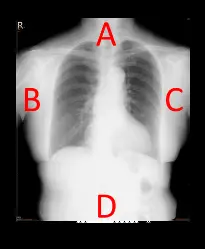

進行胸部診斷攝影時,若病人擺位許可,陰極應擺放在圖中那一側較為適當?

本題提供一張標準的胸部正面 X 光影像(AP 或 PA view),影像標示了四個方位:

- A側:位於影像最上方,對應人體的頸部與肺尖(Apices)。此區域大多為充滿空氣的肺部組織,且肌肉脂肪層較薄,整體組織密度與厚度最低。

- B側:位於影像左側,為病患的右側(Right side,影像左上角標有 'R'),對應右側胸壁與肩臂區域。

- C側:位於影像右側,為病患的左側(Left side),可見心臟陰影朝此側偏移。

- D側:位於影像下方,對應下胸部與上腹部。此區域包含了橫膈膜(Diaphragm)、肝臟、胃等實質臟器以及較厚的腹部軟組織,整體厚度與密度遠大於上